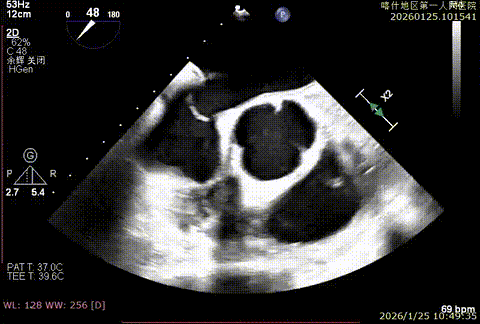

X-plan切面3区后叶脱垂

X-plan切面重度反流

该例患者为DMR类Barlows患者,二尖瓣重度反流,患者1,2,3区均可见脱垂,脱垂主要源于3区,反流主要源于3区。术前制定手术策略:使用一把XTR解决患者瓣叶脱垂与二尖瓣反流。术中进行房间隔穿刺后将XTR-CDS送入左心房,通过操控“M”旋钮,成功将二尖瓣夹定位于2区正上方。在2区进行弹道测试成功后,进行Orientation调整。在3区将二尖瓣夹送入左心室,成功捕捞和夹持瓣叶后缓慢关紧夹臂,解决大部分反流,Saide by Saide L植入第二把XTR。TEE检查见二尖瓣反流程度充分降低至1+,二尖瓣双孔组织桥稳定,跨瓣压差3mmHg,肺静脉逆流改善明显,手术安全结束。

X-plan 1区后叶脱垂

X-plan 反流情况